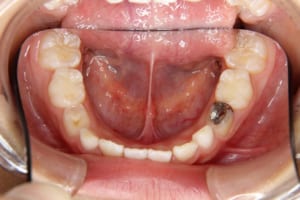

治療前

年齢・性別 8才 女子

主訴 上顎が出ている(前歯が出ている)

すきっ歯

治療内容 子どもの矯正治療(前期治療)

マルチブラケット装置を使用した大人の矯正治療(後期治療/成人矯正治療)を行いました。

使用した装置 子どもの矯正治療(前期治療)

咬合挙上板

緩徐拡大装置

大人の矯正治療(後期治療/成人矯正治療)

マルチブラケット装置(セラミックブラケットおよびシルバーワイヤー))

歯科矯正用アンカースクリュー(2本)

治療回数 子どもの矯正治療:18回(その他観察3回) 大人の矯正治療:21回

治療期間 子どもの矯正治療:3年2か月(その他観察1年0カ月) 大人の矯正治療:2年2か月

抜歯および非抜歯 上の左右第一小臼歯、右下の第一小臼歯

費用(保定除く) 884,520円(税込)